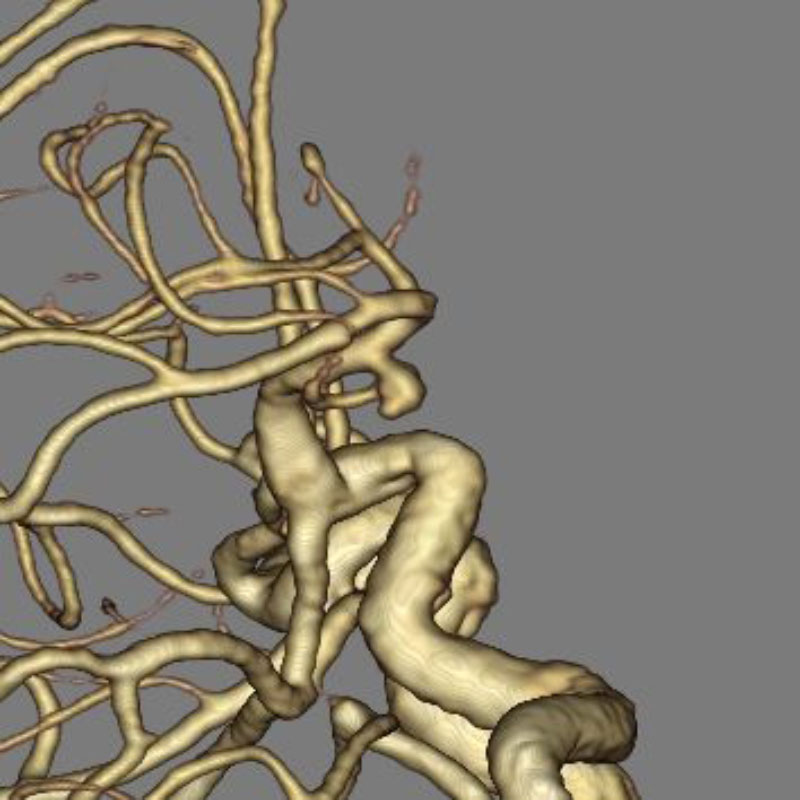

脳動静脈奇形

血管塞栓術

松田/濵田